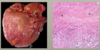

The provided images are from a 3 year old patient

What is the pathology?

Kawasaki Disease

- Left image

- marked narrowing at the lumen

- marked intimal thickening

- Right image

- organizing thrombus

- can tell because the development of new blood vessels & blood

- also, presence of fibrin

- organizing thrombus